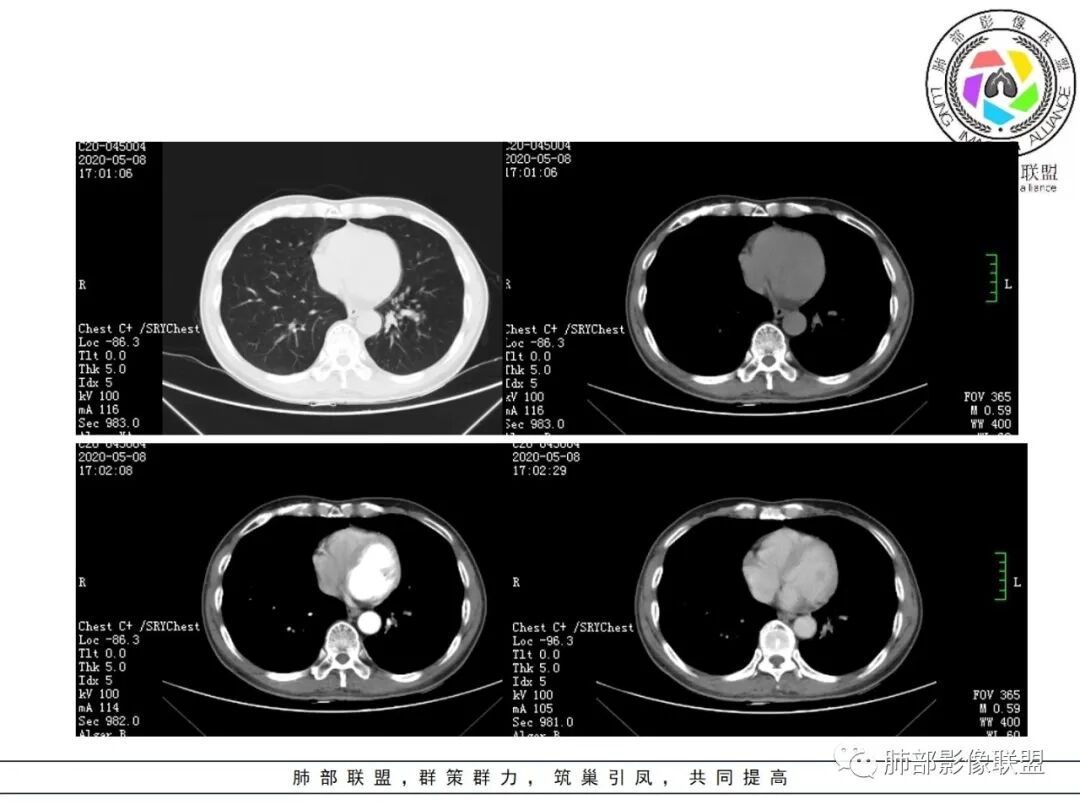

临床资料:老年男性,咳嗽咳痰2月余,慢性病史。有吸烟史40年(现已戒烟),抗感染治疗2周肺部病灶未见吸收。

影像所见:

1.关于病灶分布:本例多发小片影局限在左肺下叶,其他肺叶未见异常病灶。

2.关于支气管:上述病灶辖区外侧段支气管截断,环壁结节,远端阻塞性肺炎,是肺癌的重要征象。

4.关于临床资料:老年男性,长期吸烟史,肺气肿背景,要警惕鳞癌的可能性。

5.关于阻塞性肺炎:同一部位反复发生的感染,治疗效果不佳或反复发生,应仔细搜寻相关气道异常,警惕肿瘤导致阻塞性肺炎的可能。